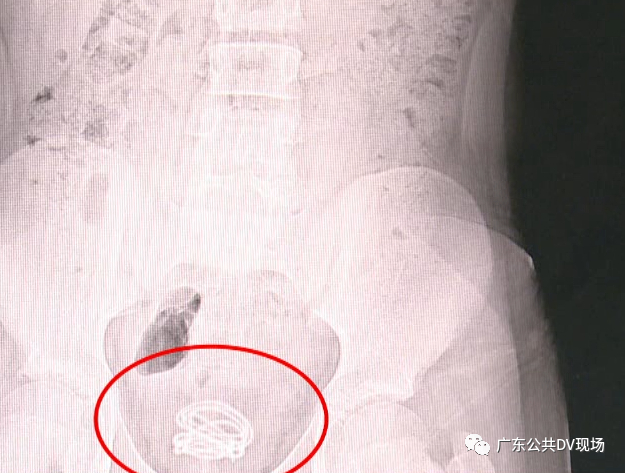

后来经X光检查

医生确实发现少年的膀胱中

有一团线圈

足足有70厘米长